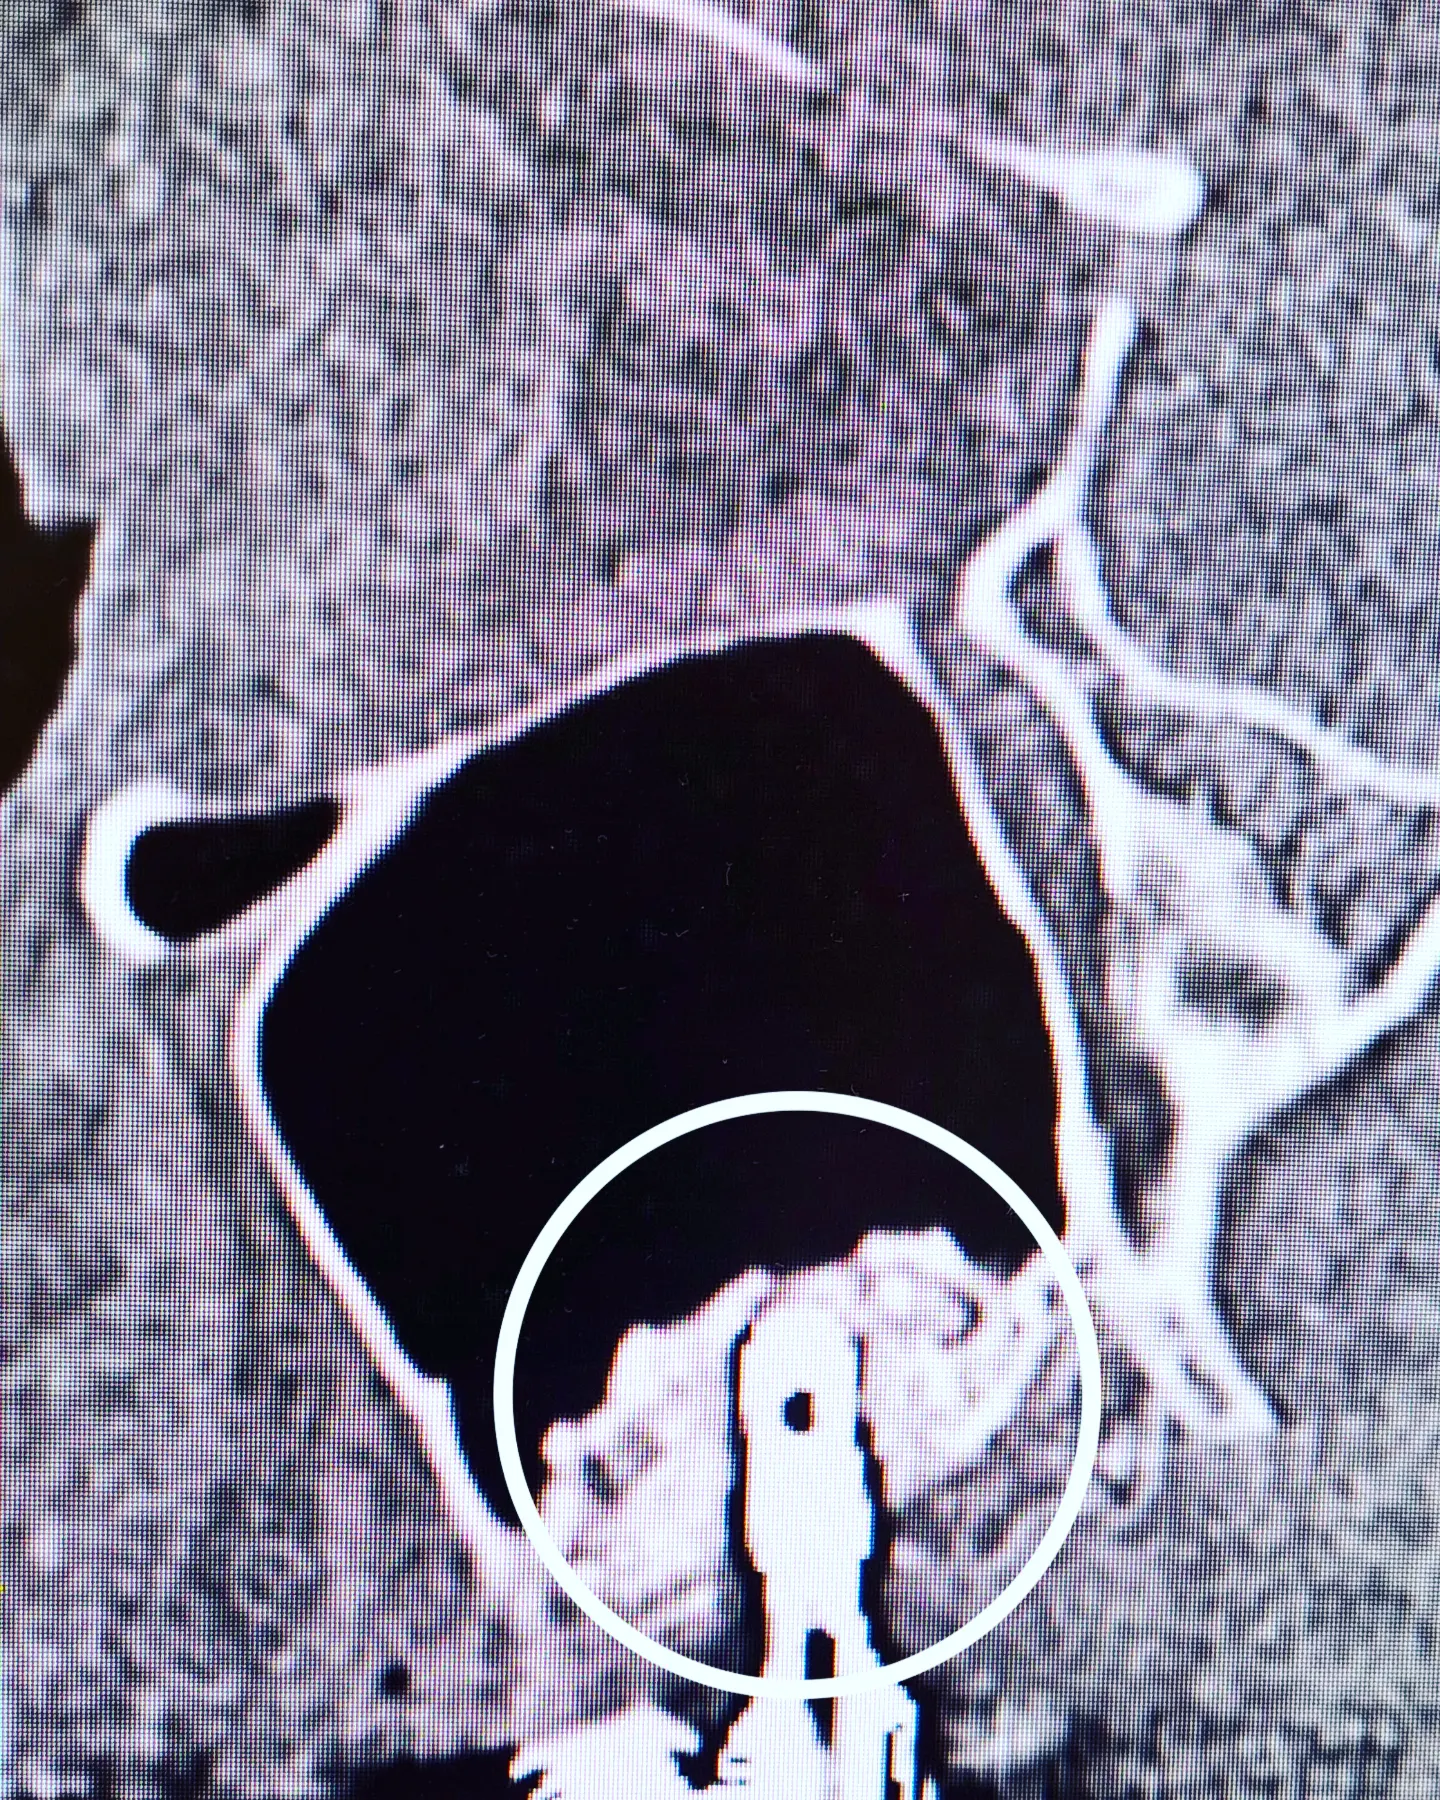

Немного занимательной стоматологии в ЛОР-практике. На приеме был пациент, которому ранее был выполнен синус-лифтинг (вдруг кому интересно как это выглядит).

Синус-лифтинг - операция по наращиванию костной ткани на верхней челюсти, когда ее не хватает для установки имплантов зубов. Почему её приходится делать? Если в челюсти отсутствует зуб, то со временем (при отсутствии нагрузки на челюсть в этом месте) атрофируется костная ткань. Для установки импланта необходимо минимум 10 мм костной ткани до гайморовой пазухи. В противном случае, показано поднятие ее дна - синус-лифтинг.